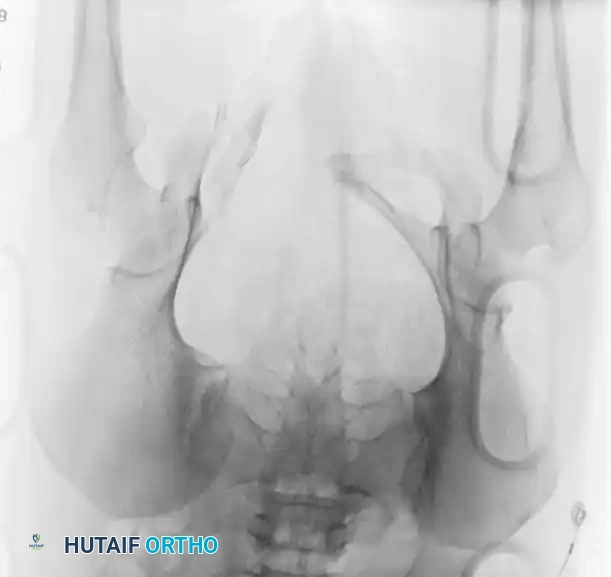

The following gallery demonstrates the progression of complex pelvic ring reconstructions, highlighting advanced imaging, intraoperative fluoroscopy, and definitive fixation constructs.

Advanced Imaging and Preoperative Planning

Image